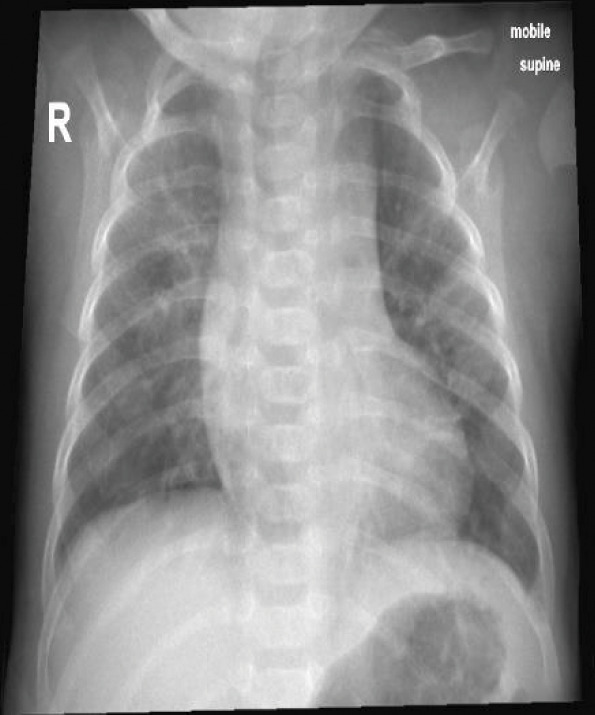

膈肌麻痹(DP)可由中枢神经系统病理或周围神经损伤引起。肋间胸引流术治疗气胸后直接损伤膈神经是一种少见的并发症。我们报告了一名4个月大的婴儿,早产27周,于2023年入住阿曼马斯喀特一家三级医院儿科重症监护室,患有严重呼吸道合胞病毒细支气管炎,需要插管和机械通气(MV)。他的病情因右侧气胸而复杂化,需要植入ICD。拔管后,患者持续呼吸急促,无法脱离无创通气。胸部x线及透视显示右侧膈球高且运动矛盾。他在右膈肌伸展术后明显好转,并于伸展术后第9天出院回家。

Diaphragmatic paralysis (DP) can occur due to central nervous system pathology or peripheral nerve injury. Direct injury to the phrenic nerve after intercostal chest drain (ICD) insertion for treatment of pneumothorax is an infrequent complication. We present a 4-month-old infant, ex-preterm 27 weeks, who was admitted to a tertiary care hospital paediatric intensive care unit in Muscat, Oman, in 2023 with severe respiratory syncytial virus bronchiolitis and required intubation and mechanical ventilation (MV). His illness was complicated by right-side pneumothorax that required ICD insertion. Post-extubation, he had persistent tachypnoea with the inability to be weaned from non-invasive ventilation. Chest X-ray (CXR) and fluoroscopy showed a high right diaphragm dome with paradoxical movements. He improved dramatically after the plication of the right diaphragm and was discharged home on the 9th day after the plication.